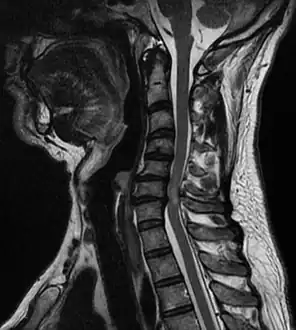

Diagnosis is by X-rays but preferably magnetic resonance imaging (MRI) of the whole spine.[2] The most common causes of cord compression are tumors, but abscesses and granulomas (e.g. in tuberculosis) are equally capable of producing the syndrome. Tumors that commonly cause cord compression are lung cancer (non-small cell type), breast cancer, prostate cancer, renal cell carcinoma, thyroid cancer, lymphoma and multiple myeloma.

-

Image indicates C5–C6 with severe spinal cord compression (and large disc herniation at C4–C5 ) -